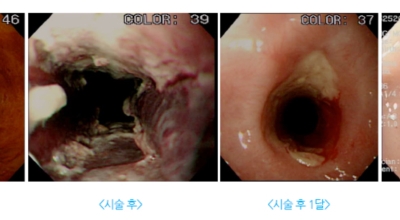

점막에 발생되는 식도암은 초기단계에서는 내시경으로 점막만 긁어내는 식으로 치료를 할 수 있습니다. 하지만 암이 자라면서 점막 하단에 있는 근육층으로 조금씩 침범을 하다 보면 주변으로 림프절 전이가 발생할 수 있기 때문에 수술을 하는 것이 원칙입니다.